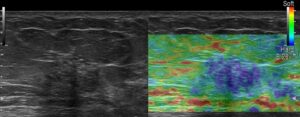

エラストグラフィーの歪み低下も確認できます。

血流シグナルとエラストグラフィーの歪み低下が見えるから

DCIS以上と考えて…

乳癌か?と考えたら、低エコーの具合がそんなに黒くない(もっと低エコーが私の乳癌のイメージです。あくまで私のイメージ)からDCISかなぁ…なんて思いつつ